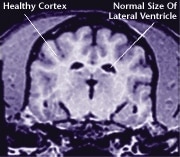

![]() Healthy Older Brain | ![]() Older Brain with Damage |

| MRI scans show loss of brain tissue in affected dogs. Note: MRI scans are not harmful to dogs. | |